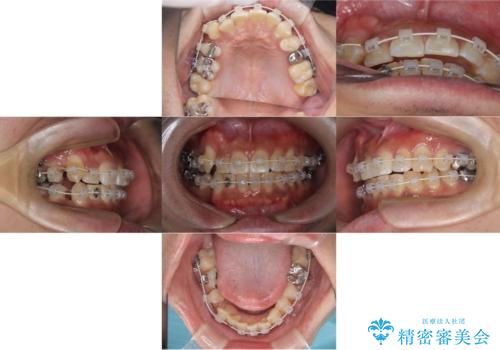

- ワイヤー矯正装置(審美装置)

右側2級、左側1関係だったため、右側上下第一小臼歯を抜歯し、ワイヤー矯正を行いました。

期間:2年6カ月